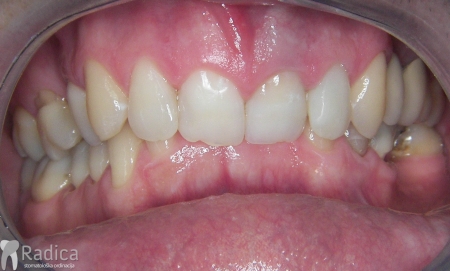

U galeriji slika su prikazani klinički slučajevi ovakvih odraslih pacijenta bilo da se radi samo o ortodontskoj terapiji ili predprotetskoj ortodonciji.

Na sljedećoj slici mogu se vidjeti početak i kraj ortodontske terapije. Pacijentica je upućena od svog stomatologa nakon što nije bila zadovoljna izgledom osmjeha i odnosom zuba i gingive u privremenom protetskom radu. Napravljena je ortodontska terapija samo u gornjoj čeljusti a nakon toga novi privremeni protetski rad.